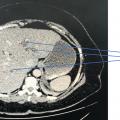

Carcinome hépatocellulaire

TUMEURS DU FOIE

Image